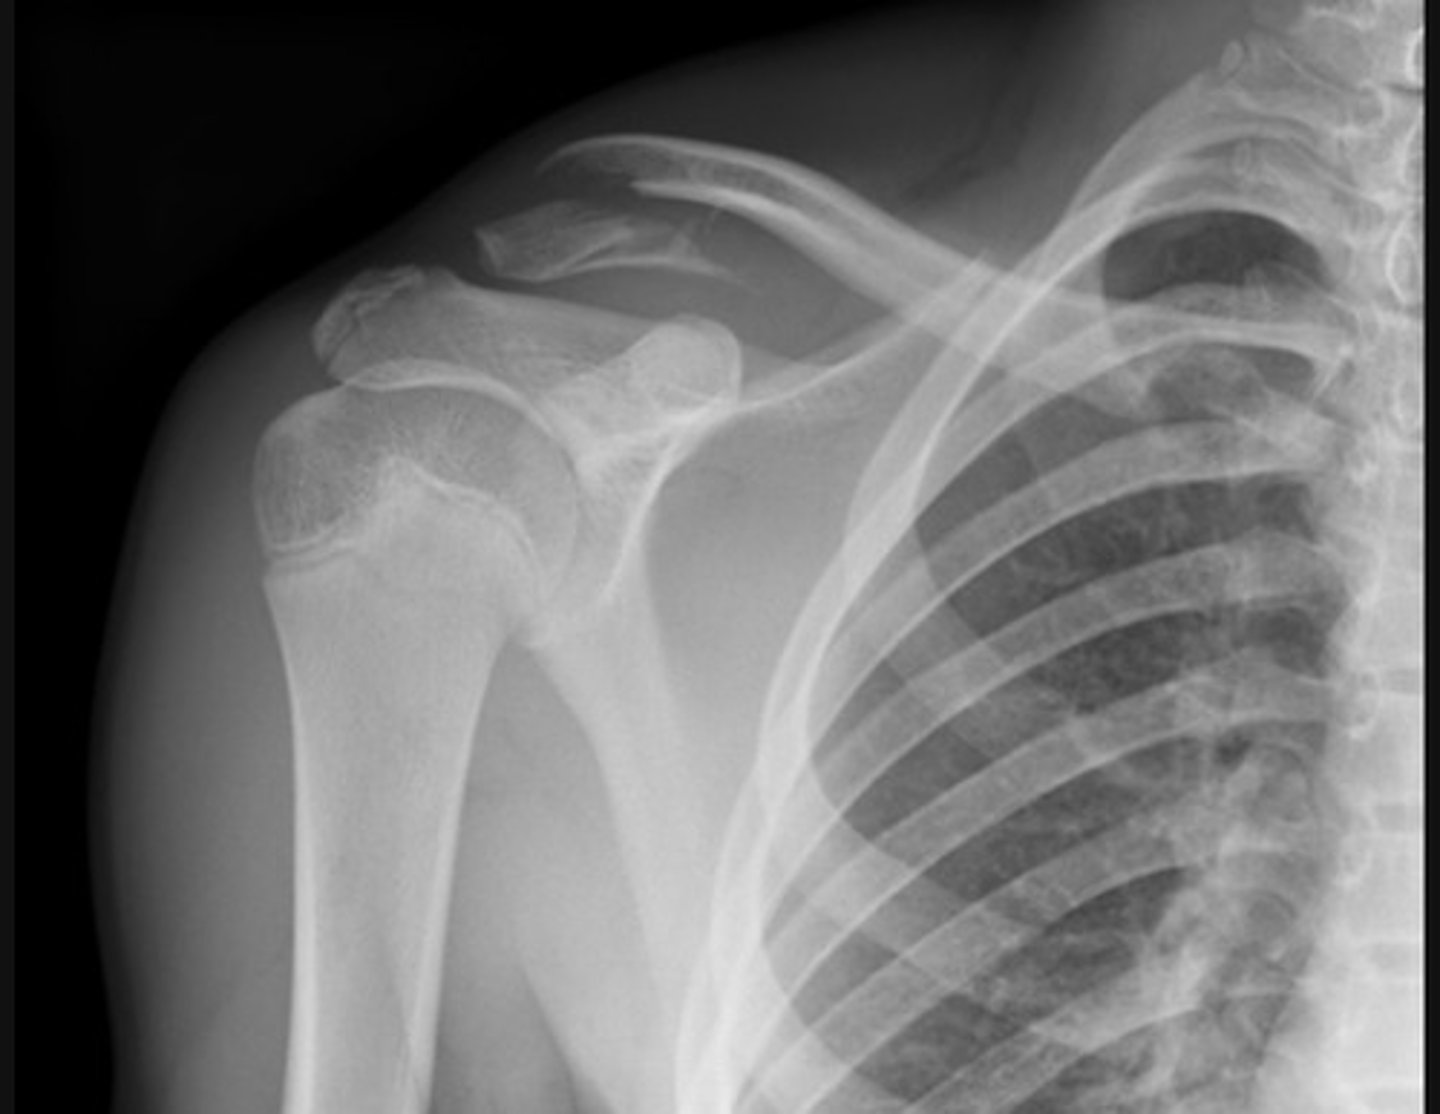

Anterior dislocation. The humeral head is dislocated from the glenoid of the scapula and is now located inferior to the coracoid process of the scapula.

This shoulder anterior dislocation is complicated by a greater tubercle fracture of the humeral head